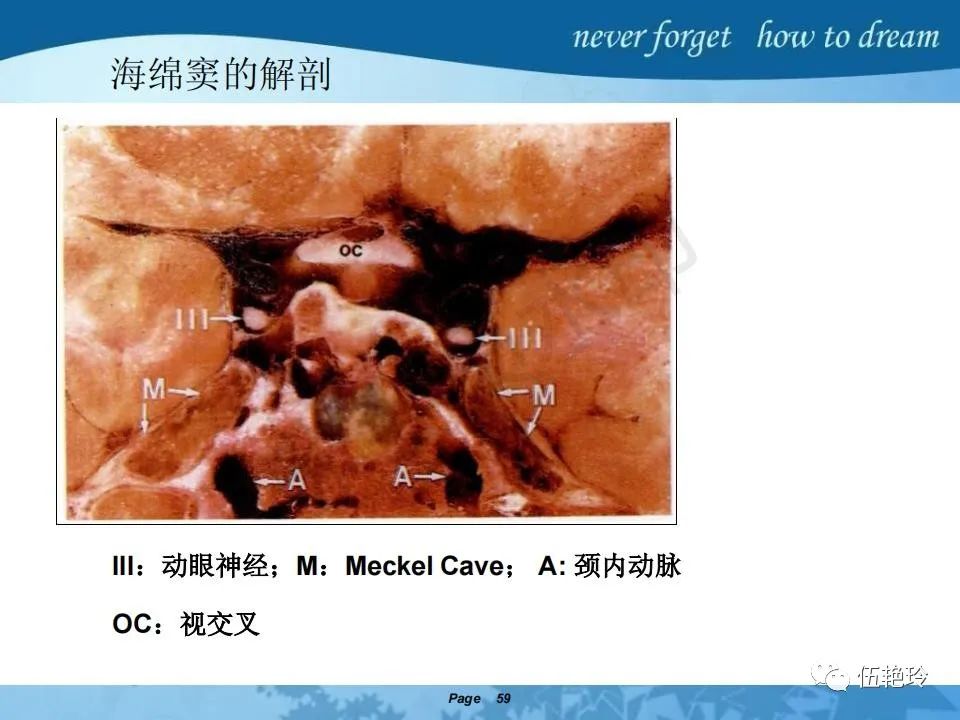

海绵窦区的解剖结构与鼻咽癌侵犯